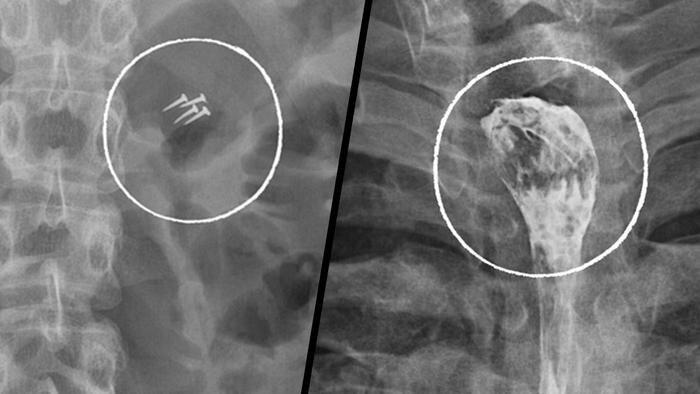

За год медикам пришлось удалять беспроводные наушники, зубные коронки, абрикосовую косточку, черенок ложки, украшения и даже гвозди, которые пациенты случайно проглотили, в том числе во время ремонтных работ.

Извлечённые предметы из пациентов НИИ скорой помощи имени Н. В. Склифосовского. Фото © Telegram / Склиф